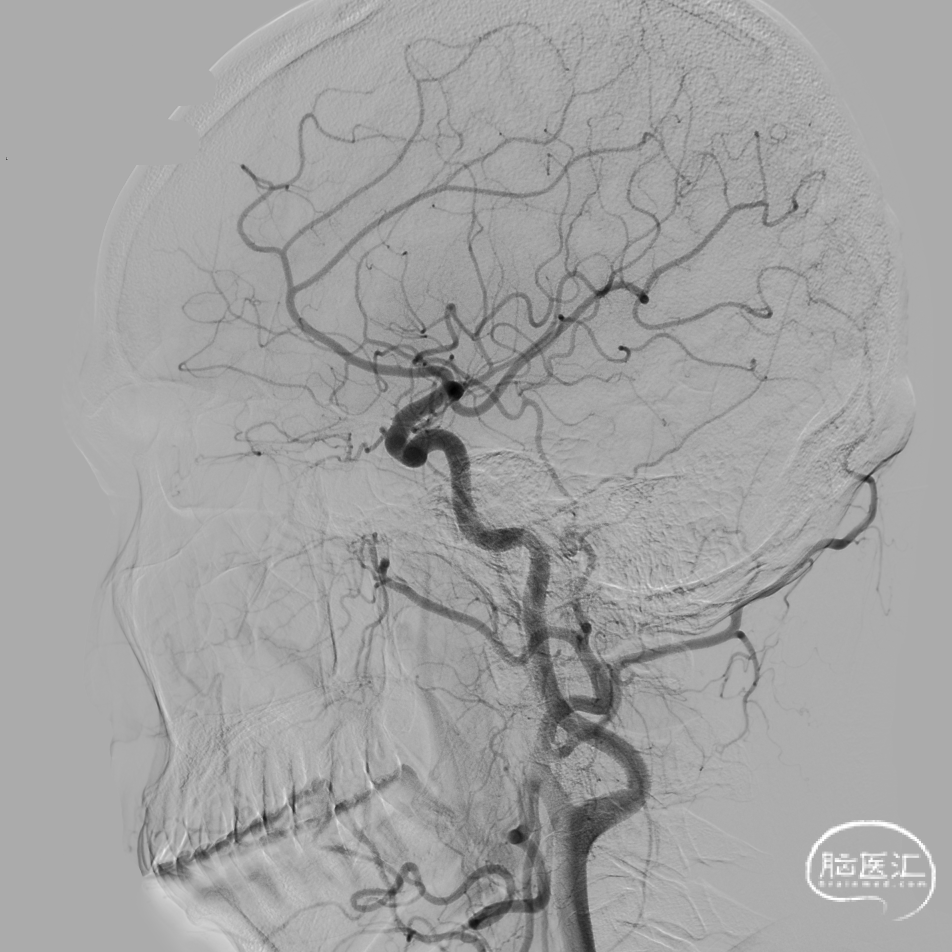

DSA:DSA提示右侧大脑中动脉M1段动脉瘤,左侧大脑前动脉A1段发育不良。

术前诊断:动脉瘤位于M1主干,考虑夹层动脉瘤可能大。

微导管到位:Synchro微导丝引领支架微导管通过病变血管进入大脑中动脉M2段。

支架到位,原位释放,前段打开。

造影确认支架远端打开充分,贴壁良好,继续推送支架。

支架全部释放,调整张力,微导管通过支架,回收输送导丝。

支架内使用成襻微导丝进行按摩,使支架充分贴壁。

术后造影:支架充分覆盖动脉瘤瘤颈,贴壁良好,瘤体内可见造影剂滞留。

术后支架显影:定位精准,未覆盖颞前动脉及大脑前动脉。